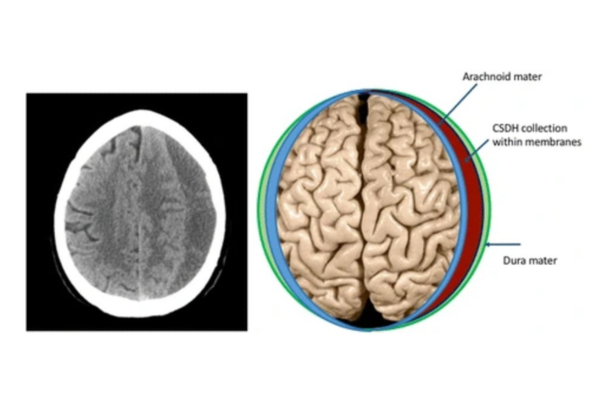

Chronic Subdural Hematoma (CSDH) is a common neurosurgical condition in which blood slowly collects between the brain and its outer covering (dura), often weeks after a minor head injury. It is frequently seen in elderly patients, individuals on blood thinners, or those with a history of trivial trauma that may even be forgotten.

•CT Scan Brain – most commonly used and quickly identifies the hematoma